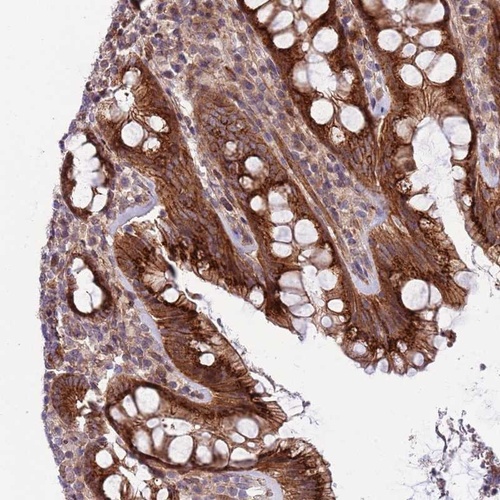

Immunohistochemical staining of human rectum shows strong cytoplasmic and membranous positivity in granular pattern in glandular cells.